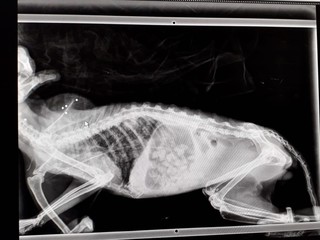

Un vecchio gatto di una colonia felina a Noli è stato soccorso, con difficoltà respiratorie, dai volontari dell’associazione A-mici di Nella, affiliata alla Protezione Animali savonese; si temevano problemi dovuti all’età (ha più di 10 anni) ma le radiografie hanno rilevato la presenza di cinque pallini di fucile da caccia che gli rendono difficile la respirazione.